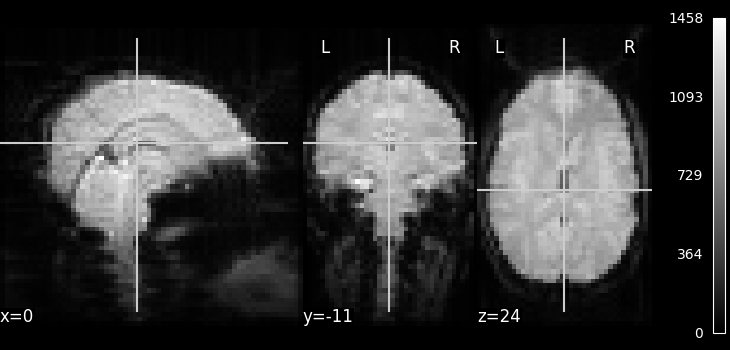

Visualization¶

from nilearn.image.image import mean_img

# Compute the mean EPI: we do the mean along the axis 3, which is time

func_filename = haxby_dataset.func[0]

mean_haxby = mean_img(func_filename)

from nilearn.plotting import plot_epi, show

plot_epi(mean_haxby, cbar_tick_format="%i")